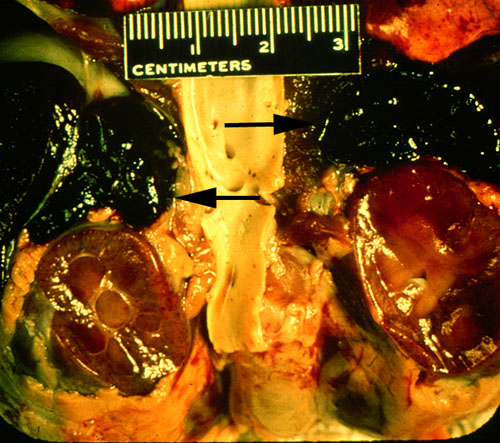

Adrenals, Waterhouse Friderichsen syndrome, gross

The adrenals in Waterhouse Friderichsen syndrome are hemorrhagic due to microthrombi, which cause infarction. The adrenal insufficiency that results creates hypotension that is unresponsive to fluid resuscitation. Corticosteroids must be given. It is usually seen in meningococcemia (Neisseria meningitidus), but can occur with other Gram-negative infections, or in DIC from any cause.